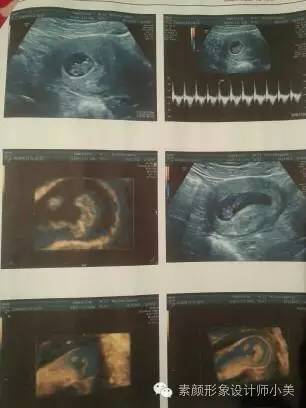

9周胎儿发育

进入第9周,你的胚胎从现在开始可以称为“胎儿”了,也可以称之为“小宝宝”。为了接纳新居民,你的子宫膨胀得非常大,现在胎儿的尺寸大约有25毫米,而且胎儿许多位置都有所改变,如胚胎期的小尾巴不见了等。现在所有的器官、肌肉、神经开始工作。手部从手段开始变得稍微有些弯曲,双脚开始摆脱蹼状的外表,眼帘开始覆盖住眼睛。